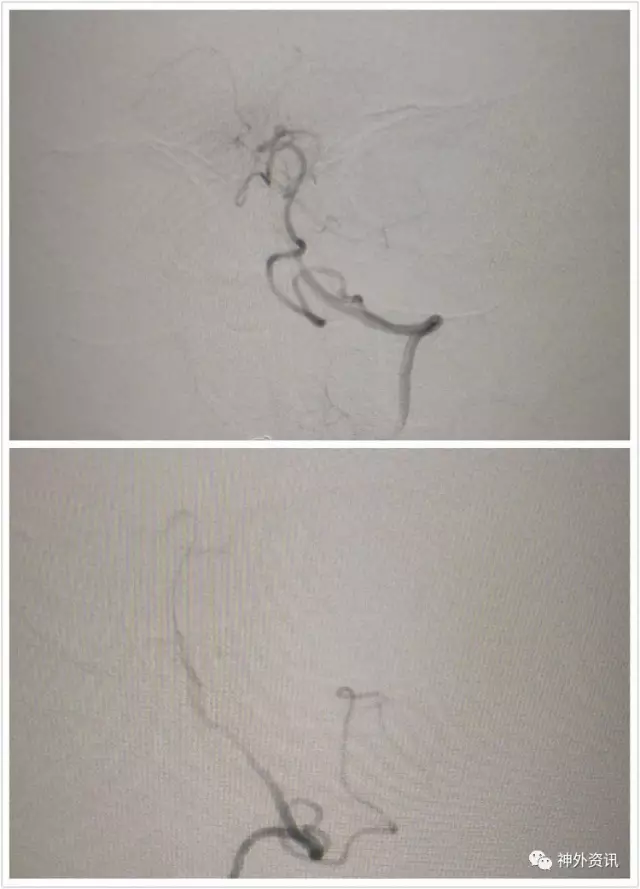

L一VA开口重度狭窄

L-VA正侧位:颅内段各血管显影尚好,左侧PⅠCA供血双侧

R一VA正位:该侧血管管径较粗,应为优势侧,然而同侧PICA/AICA显影不好,头晕原因仍未知道

L一VA开口支架成形满意,术后病人症状缓解

正位造影看不到左ⅤA,开口段内膜过度增生闭了

L-VA晚间可见肌支吻合与VA相通,闭塞节段限于开口段,可否一试把支架与增生内膜斑块取了再通呢?